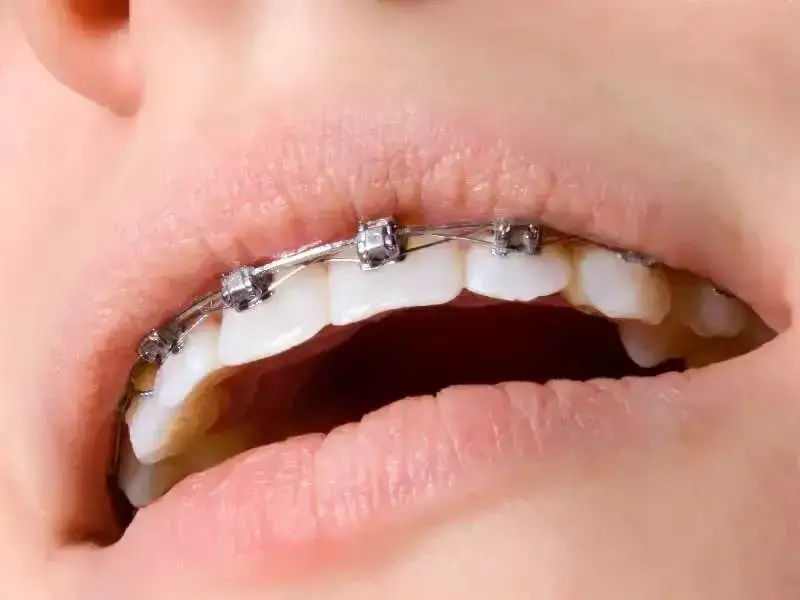

Na jakie zęby zakłada się aparat? Poznaj rodzaje aparatów ortodontycznych, proces leczenia wad zgryzu i dowiedz się, jak działa aparat na zęby przednie i tylne.